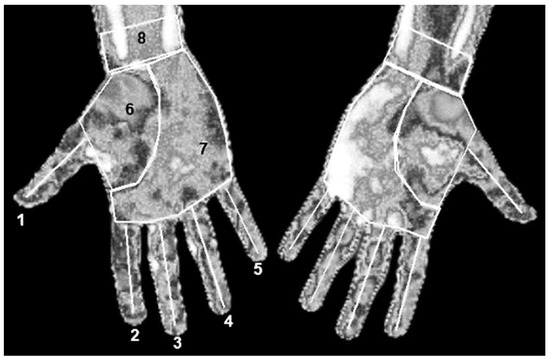

The mean Tsk of 8 regions of interest (ROIs) of each hand (Figure 2) was obtained using thermography software (Thermacam Researcher Pro 2.10 software, FLIR, Wilsonville, OR, USA) and considering an emissivity of 0.98 [20]. Three variables were calculated: (1) Asymmetry: Tsk difference of each ROI between non-dominant and dominant hand, (2) Variation: Tsk difference of each ROI between the baseline and the post-match measurement moment of athletes, and (3) CST Variation: Tsk difference of each ROI between immediately after and each minute after CST.

Figure 2.

Regions of interest determined. (1) Thumb; (2) Index finger; (3) Middle finger; (4) Ring finger; (5) Little finger; (6) Thenar eminence; (7) Palm without thenar eminence; (8) Wrist.